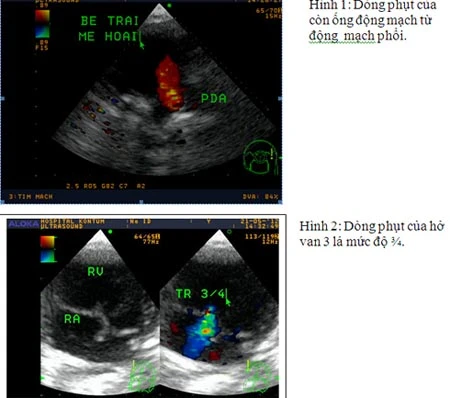

Kết quả siêu âm tim con của sản phụ Hoài sau khi được hỗ trợ sinh non. Ảnh do bệnh viện cung cấp.

"Trong thời gian nằm ở khoa nhi cấp cứu, cháu được siêu âm tim còn phát hiện thêm dị tật ống động mạch (PDA) và hở van 3 lá có tăng áp phổi nặng. Rõ ràng cháu có đa dị tật rất nặng", bác sĩ Trưởng khoa chẩn đoán hình ảnh Bệnh viện đa khoa Kon Tum nói. Em bé sau đó đã qua đời.